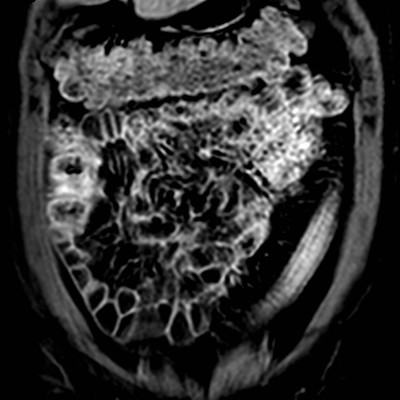

März 2017 von PD Dr. Peter Bannas aus Hamburg

Frage 1: Um welche Bildmodalität handelt es sich?

- a) MRT (native T2w-Sequenz sowie T1w-Sequenz mit Kontrastmittel)

- b) MRT (native T2w-Sequenz sowie native T1w-Sequenz)

- c) CT (portalvenöse und arterielle Phase)

- d) PET/CT (CT im Weichteilfenster und PET)

- e) CT (native und arterielle Phase)

Frage 2: Was führt in der benutzten Aufnahmetechnik am wenigsten wahrscheinlich zu Artefakten?

- a) Metallische Prothesen

- b) Luftansammlungen im Darm

- c) Bewegungen des Patienten während der Aufnahme

- d) Blutfluss

- e) Nierenzysten

Frage 3: Welche Struktur ist nicht erfasst?

- a) Colon descendens

- b) Colon ascendens

- c) Colon transversum

- d) Nieren

- e) Leber

Frage 4: Welcher Befund ist nicht vorhanden?

- a) Zielscheiben-Phänomen (Target-Sign)

- b) Ödem in der Submukosa

- c) Langstreckiger Verlust der Haustrierung

- d) Kontrastmittelanreicherung der Darmwand

- e) Pneumatosis intestinalis

Frage 5: Welche Diagnose stellen Sie?

- a) Colitis ulcerosa

- b) Colonkarzinom

- c) Lymphom

- d) Leiomyom

- e) Metastase

Preisfrage: Welche Erkrankung ist mit der Colitis Ulcerosa assoziiert?

- a) Primär biliäre Cholangitis

- b) Primär sklerosierende Cholangitis